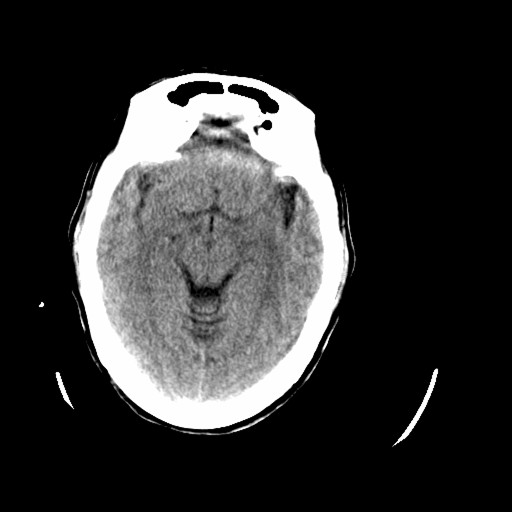

标题: CT16233:女,44岁,智障多年,现感头痛 [打印本页]

标题: CT16233:女,44岁,智障多年,现感头痛

小脑有啥病变?

橄榄桥小脑萎缩.左侧小脑脚腔梗.

为什么不考虑发育畸形呢

1)小脑萎缩。2)小脑蚓部发育不良。

橄榄桥小脑萎缩可能,建议mri进一步检查以进一步排查。

橄榄桥小脑萎缩